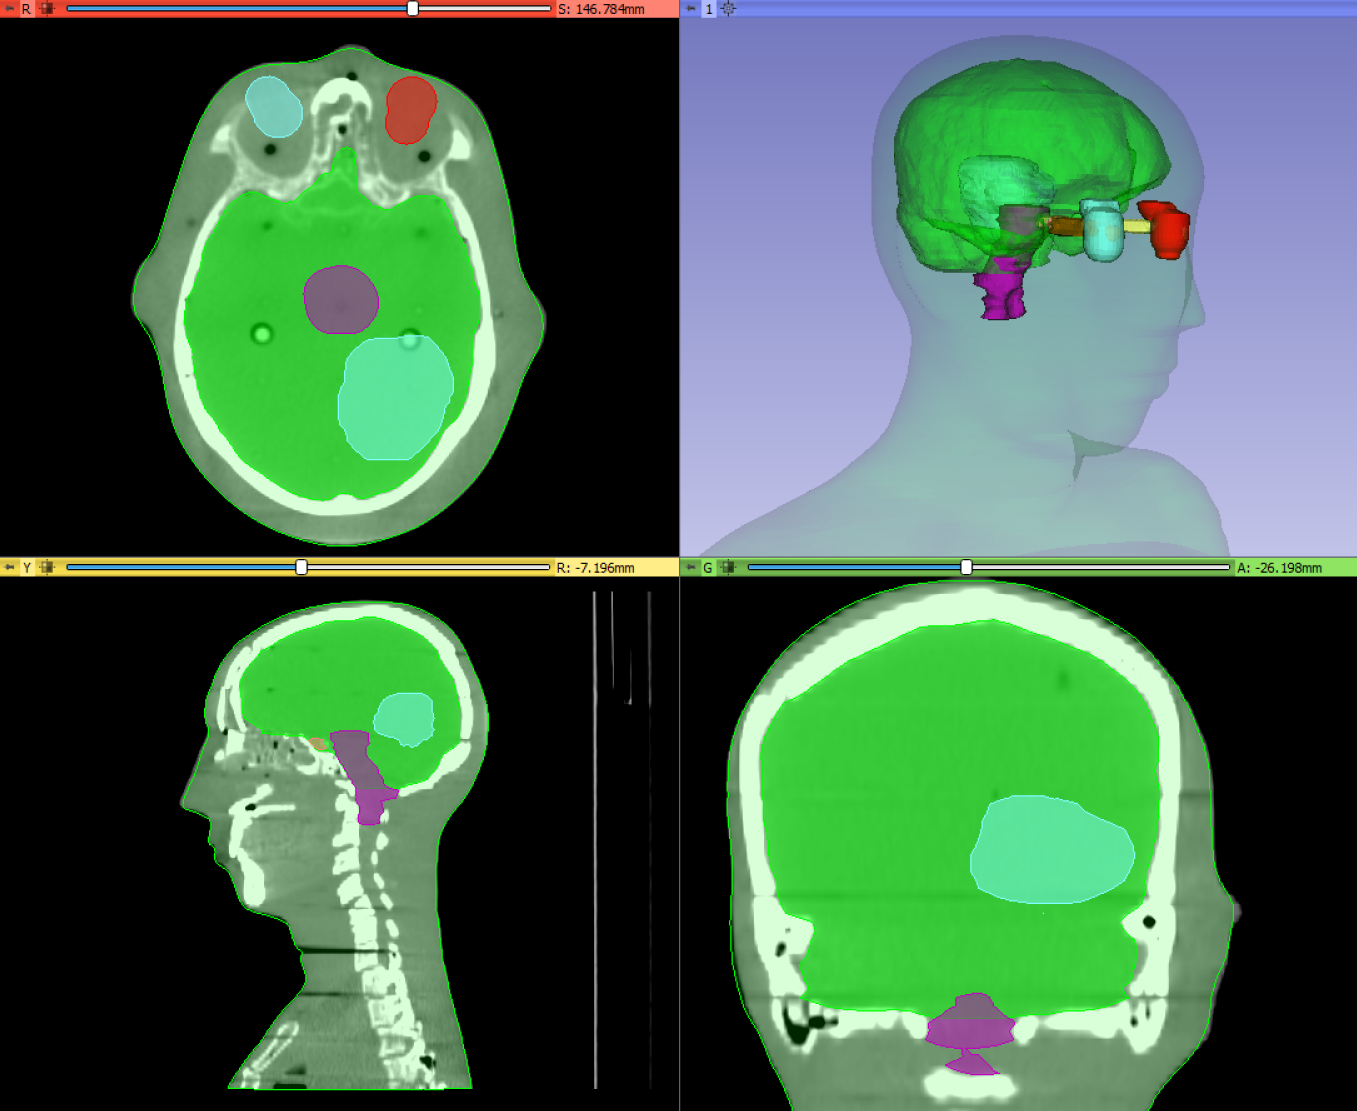

图像分割(也称为轮廓绘制或注释)是一种在图像中划定区域的程序,通常对应于解剖结构、病变和各种其他对象空间。它是医学图像计算中非常常见的程序,因为它是可视化某些结构、定量分析(测量体积、表面、形状属性)、3D打印和遮罩(将处理或分析限制在特定区域)等所必需的。

分割可以手动进行,例如通过遍历图像的所有切片并在边界处绘制轮廓;但通常使用半自动或全自动方法。Segment Editor模块提供了多种分割方法。

分割的结果存储在3D Slicer中的segmentation节点中。一个分割节点由多个段组成。

一个段指定单个结构的区域。每个段都有许多属性,如名称、首选显示颜色、内容描述(能够存储标准DICOM编码条目)和自定义属性。段可以在空间上相互重叠。

一个区域可以用不同的方式表示,例如作为二进制标签图(每个体素的值指定该体素是在区域内还是区域外)或闭合表面(表面网格定义区域的边界)。没有一种表示方式适用于所有情况:每种表示方式都有其优缺点,并根据需要使用。

| 二进制标签图 | 闭合表面 | 分数标签图 | 平面轮廓,带状 |

|---|---|---|---|

|  |  |  |

| 简单的2D查看和编辑, 总是有效(即使 变换或编辑后) | 简单的3D可视化 | 相当容易的2D查看 和编辑, 总是有效, 相当准确 | 准确的2D查看和编辑 |

| 不准确(有限的分辨率), 如果允许重叠则需要大量内存 | 难以编辑, 可能无效 (例如,自相交), 特别是在非线性 变换后 | 需要大量内存 | 在3D中模棱两可, 质量差 3D可视化 |

每个段存储在多个表示中。一个表示被指定为源表示(在用户界面上标有“金星”)。源表示是唯一可编辑的表示,它是保存到文件时唯一存储的表示,所有其他表示都是从它自动计算的。